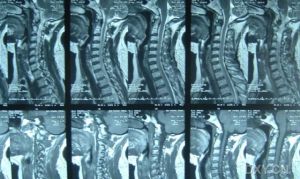

臨床表現

痙攣性斜頸1.痙攣性斜頸的程度可分輕、中、重三度。輕型者肌痙攣的範圍較小,僅有單側發作,無肌痛;中型者雙側發作,有輕度肌痛;重型者不僅雙側頸肌受到連累,並有向鄰近肌群,如肩部、顏面、胸肌及背部長肌群蔓延的趨勢,且有嚴重肌痛。

2.痙攣性斜頸的臨床表現可以分成四種型別。

(1)鏇轉型:頭繞身體縱軸向一側做痙攣性或陣攣性鏇轉。根據頭與縱軸有無傾斜,可以分為三種亞型:水平鏇轉、後仰鏇轉和前屈鏇轉。鏇轉型是本病最常見的一種型別,其中以後仰型略為多見,水平型次之,前屈型較少。此外根據肌肉收縮的情況,又可分為痙攣和陣攣兩種。前者患者頭部持久強直地鏇向一側;後者則呈頻頻來迴旋動。

(2)後仰型:患者頭部痙攣性或陣攣性後仰,面部朝天。

(3)前屈型:患者頭部向胸前做痙攣性或陣攣性前屈。

(4)側攣型:患者頭部偏離縱軸向左或右側轉,重症患者的耳、顳部可與肩膀逼近或貼緊,並常伴同側肩膀上抬現象。